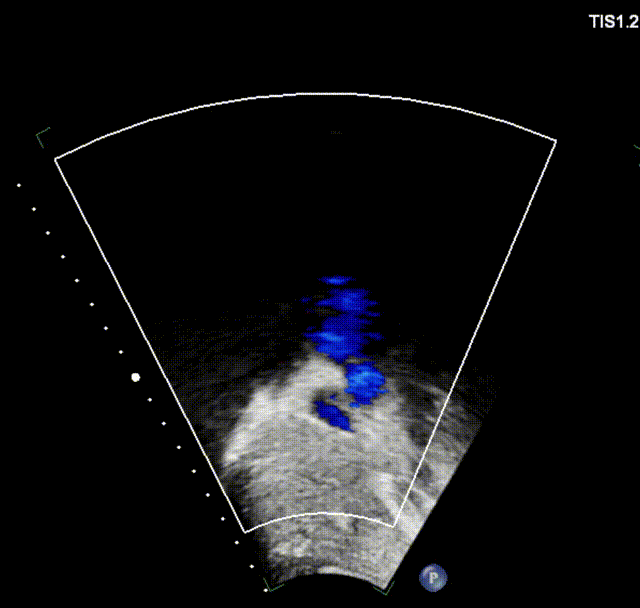

室早RFCA+ASD介入病例(上:术后6个月心超;下:术后12个月心超)

上述良好的短中期随访结果验证了可降解封堵器在儿童ASD介入治疗中的安全性与有效性,期待更长期的随访数据进一步验证远期效果。